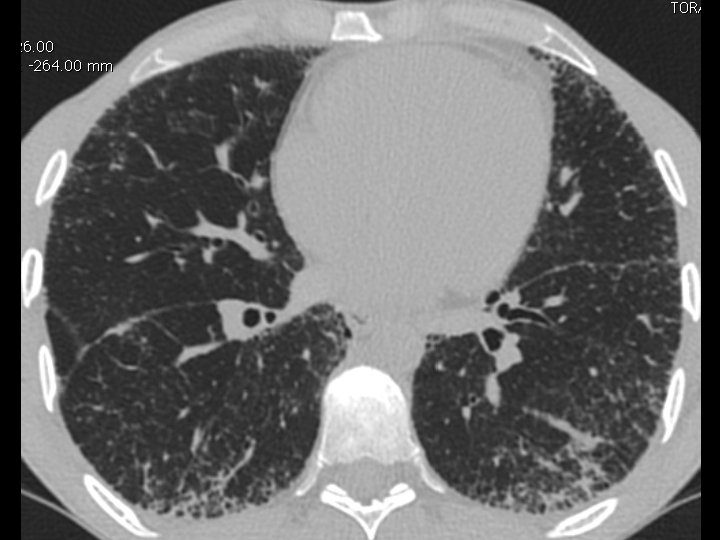

High-resolution CT scan

Subpleural, basal predominance Reticular abnormality Honeycombing with traction bronchiectasis UIPUIP Pattern

Subpleural, basal predominance Reticular abnormality Honeycombing with traction bronchiectasis Profuse micronodules UIPUIP Pattern Inconsistent with UIP Pattern

39 yo caucasian male, works in car collision repair and painting Multiple allergies, Gastroesophageal reflux disease and Thrombocytopenia of unknown etiology Smoker. No drugs CT: Reticular abnormality and honeycombing of subpleural basal predominance + micronodules Lung function tests: decreased diffusion capacity of the lung Blood tests: small increase of ESR and CRP; Autoimmune screening blood tests were normal BAL: normal celularity, with a mild increase in the neutrophil and eosinophil count

39 yo caucasian male, works in car collision repair and painting Multiple allergies, Gastroesophageal reflux disease and Thrombocytopenia of unknown etiology Smoker. No drugs CT: Reticular abnormality and honeycombing of subpleural basal predominance + micronodules Lung function tests: decreased diffusion capacity of the lung Blood tests: small increase of ESR and CRP; Autoimmune Screening Blood Tests were normal BAL: normal celularity, with a mild increase in the neutrophil and eosinophil count Definitive diagnosis can be established? Additional diagnostic tests required? Which tests?